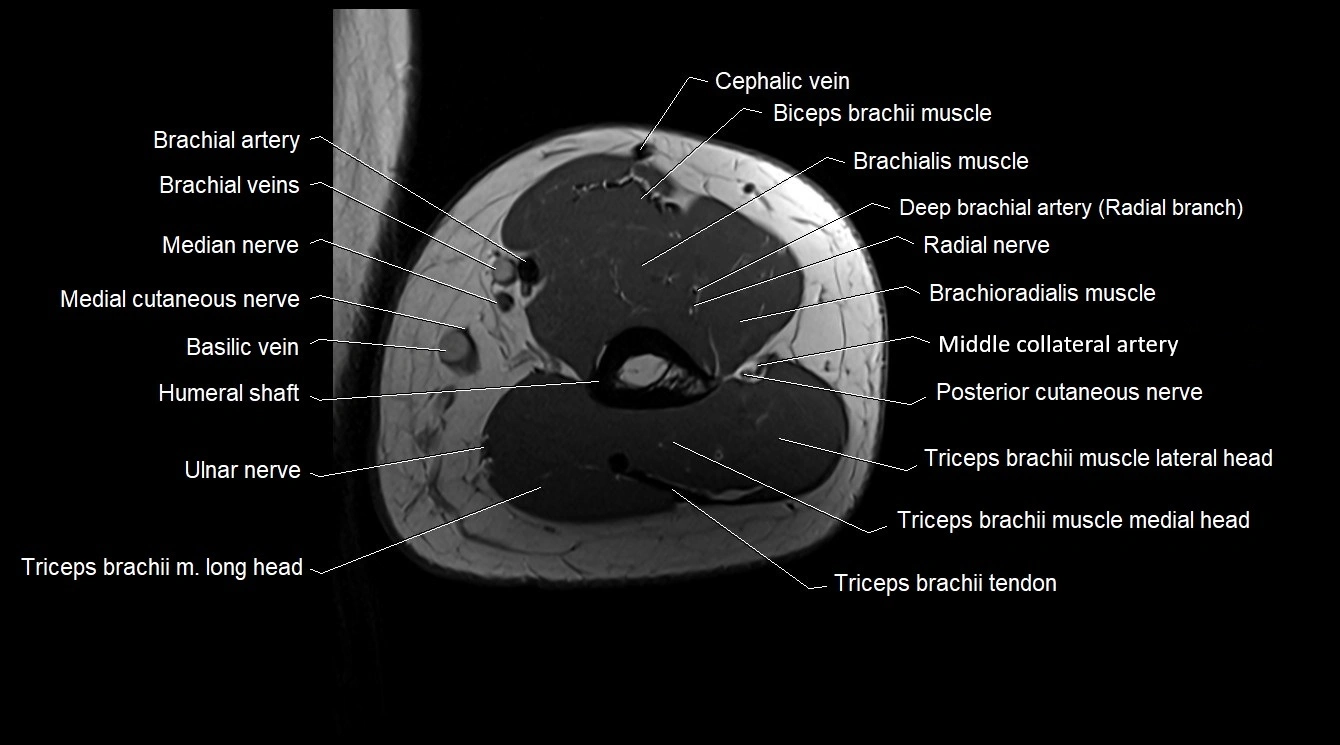

MRI image

CT image